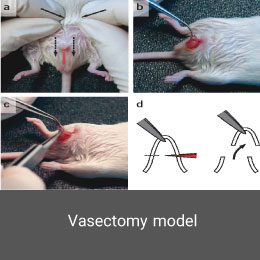

- Surgery and biopsy

- Create and induce a variety of animal models